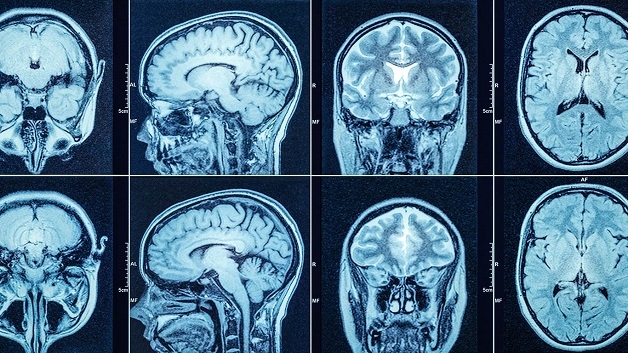

Chụp CT sọ não là chỉ định cận lâm sàng giúp bác sĩ kiểm tra bệnh nhân có triệu chứng vùng đầu – mặt do hoặc không do chấn thương như hôn mê, đau đầu, chóng mặt,… Kĩ thuật này sử dụng tia X quét từ gốc mũi (Đường OM) đến đỉnh đầu người bệnh để lấy hình ảnh chi tiết trong sọ não. Đầu phát tia của máy sẽ nghiêng về nhiều hướng khác nhau để ghi lại các hình ảnh, dữ liệu được truyền về và lưu trữ trong máu tính, dựng thành hình ảnh 2D hoặc 3D hỗ trợ chẩn đoán.

Chụp CT sọ não là kĩ thuật chẩn đoán hình ảnh hiện đại giúp xác định các tổn thương vùng đầu – mặt.

Kết quả chụp CT sọ não hiển thị dưới hình ảnh cắt lát.